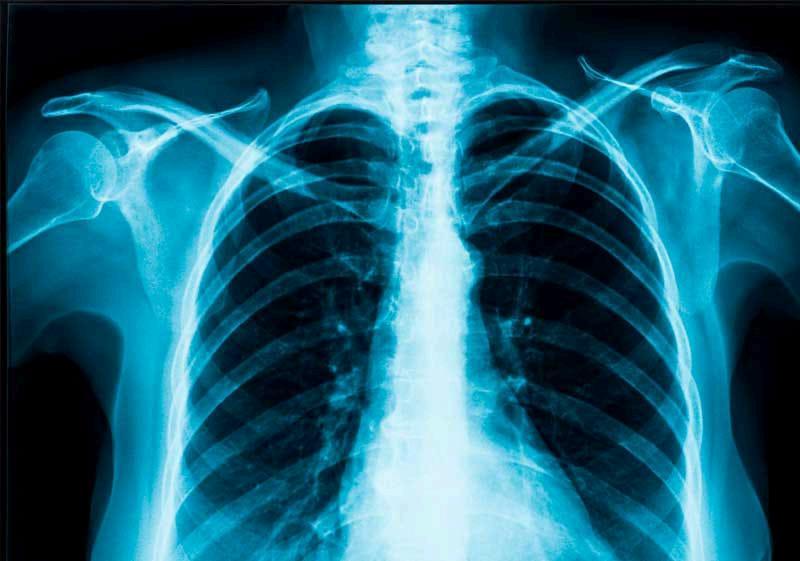

Radiografíadetórax:índicecardiotoráciconormal,hiliosengrosadosconadenopatíascalcificadas Siluetacardiomediastínicayparénquimassinotroshallazgos

Radiografiadetorax

Diagnósticoyprocedimiento Imagen

ExamendediagnósticoporrayosX queproduceimágenesdelcorazón,los pulmones,lasvíasrespiratorias,los vasossanguíneosyloshuesosdela columnayeltórax esunadelosexámenesmásutilizados anteunasospechadeenfermedad,así mismopuedenrevelardetallesenel cuerpocomo:

● Elestadodelospulmones

● Problemaspulmonares relacionadosconelcorazón

● Eltamañoyelcontornodel corazón

● Vasossanguíneos

● Calcificación

● Facturas